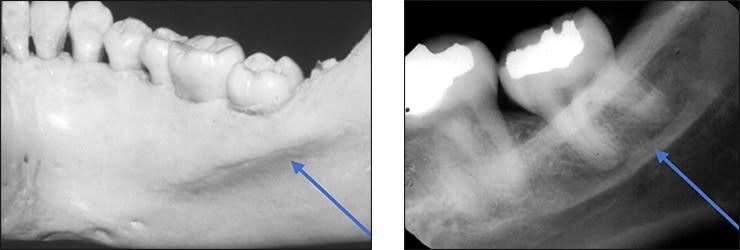

6) Mandibular Posterior Landmarks

• External oblique ridge – The external oblique ridge or line is the bony anterior border of the ramus located on the outer aspect of the mandible. This ridge has a downward diagonal course. Radiopaque.

• Internal oblique ridge – Irregular crest of bone on lingual surface of body of mandible. It runs parallel to but below the external oblique ridge. The internal oblique ridge is sometimes referred to as the mylohyoid line.

• Mandibular canal – Tube like passage through bone that travels along the length of mandible in contact with the apex of third molar.It is also referred to as the inferior alveolar nerve canal.

• Submandibular fossa – It is scooped but depressed area on bone located lingually below the myelohyoid ridge.This structure is also referred to as the submandibular gland fossa or mandibular fossa.

• Inferior border of mandible is the lower most part of the mandible. Appears as dense broad radiopaque band of bone.